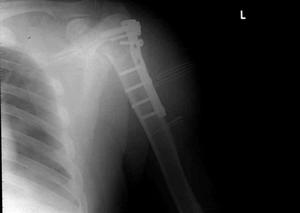

(3)固定:單純復位者,仍按前法行屈曲位下肢石膏固定,2~3周后更換功能位石膏。對需內固定者可酌情選用L型鋼板螺釘、Ender釘或其他內固定物(圖2),然後外加石膏托保護2~3周。